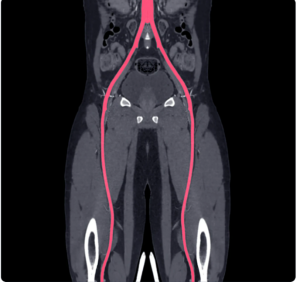

Figure 1: Femoral arteries in groin area for bypass